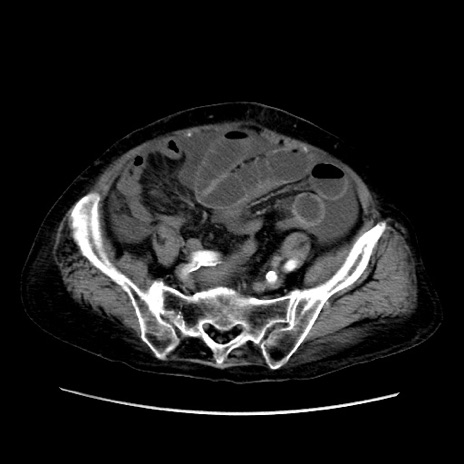

矢状断像